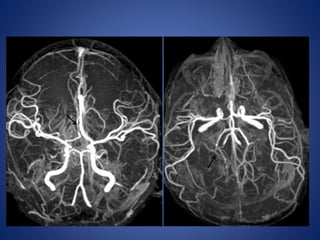

Moya Moya

• Chronic progressive arteriopathy of unknown cause and has

become one of the most common causes of pediatric stroke.

• Suzuki and Kodama classified the evolution of moyamoya disease

using angiographic findings to define six phases of the disease:

Stage 1- Narrowing of carotid fork.

Stage 2- Initiation of basal moyamoya.

Stage 3- Intensification of moyamoya

Stage 4- Minimization of moyamoya.

Stage 5- Reduction of moyamoya .

Stage 6- Disappearance of moyamoya.

• Stenosis/occlusion of the distal ICA

• moyamoya vessels with signal voids in the basal ganglia

• ischemia

• infarction

• atrophy, and ventriculomegaly.

• Small abnormal net-like vessels proliferate giving "puff of smoke"

appearance.

• Contrast-enhanced T1WI - marked leptomeningeal enhancement

along the cortical sulci (ivy sign).

often show contrast stagnating in slow-flowing collateral

vessels both in the brain parenchymal and over its surface.

MR imaging

5 yrs male child with history of left sided focal seizures with secondary generalization